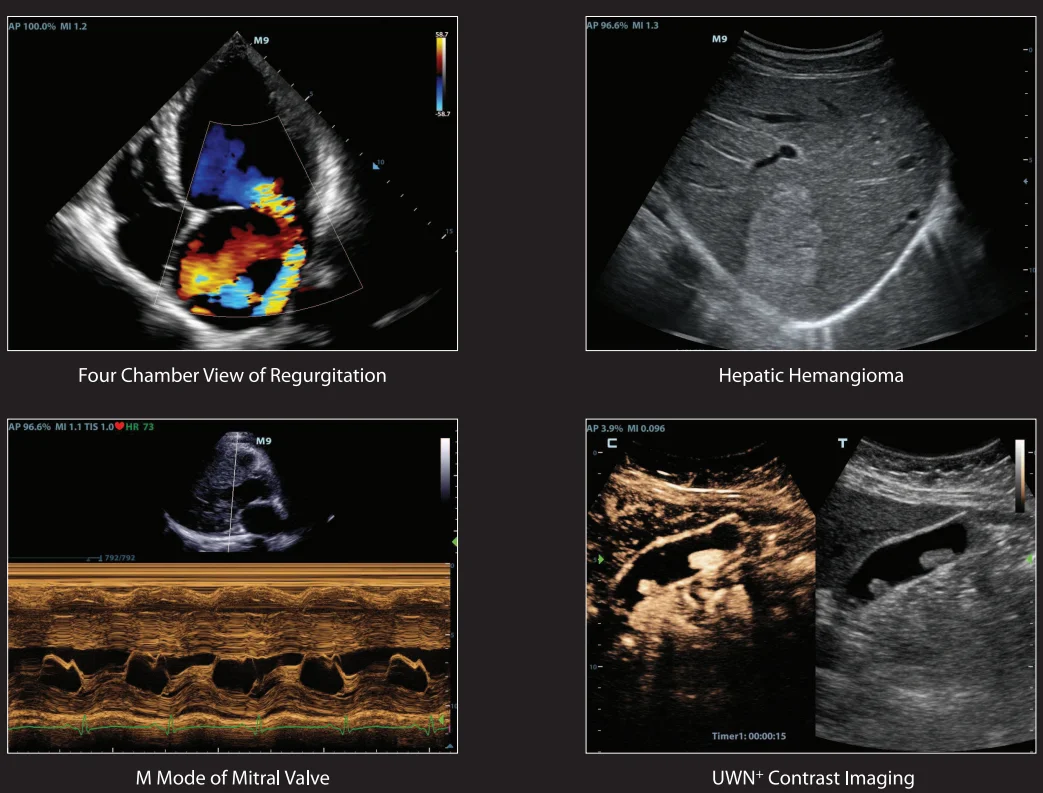

Echo Boost™ Mindray’s unique adaptive signal processing technology with intelligent echo detection, designed to utilize the native signal-to-noise information to enhance the weak echo signals while suppressing the surrounding clutter noise, providing more balanced image brightness and improved visualization of myocardium tissue layers. |